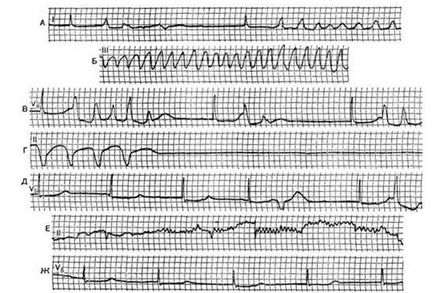

A diagnózis a szindróma MAC fő hangsúlyt kap az EKG technikák - nyugalmi EKG, napi követése. ultrahang, angiográfia lehet nevezni, hogy tisztábban lássuk a szívbetegség. Ugyanilyen fontos a hallgatózás, ha orvos is hallgathatja sajátos zajokat nyereség az első hang, az úgynevezett három tagú ritmus és így tovább. G. De hallgatózási jelek feltétlenül esnek egybe az EKG adatokat.

Mivel Adams betegség - következtében a különböző típusú vezetési zavarok, valamint a EKG-diagnosztikai kritériumok mint ilyen, nem rendelkezik, és a jelenség az EKG társított típusú ritmuszavar. által kiváltott egy adott beteg számára.

Megsértése esetén a pitvari csomópont értékelni az EKG, különösen időtartama intervalaPQ. amely tükrözi az időben a pulzus a vezetési rendszer a szinusz csomó a kamrák a szív.

Az első fokú blokád ez az intervallum nagyobb, mint 0,2 másodperc, a másodfokú intervallumot fokozatosan megnyúlt vagy magasabb, mint a normál minden szív komplexek, a QRST időszakosan csökkent, jelezve, hogy a következő impulzus csak nem érte el a kamrai szívizomban. A harmadik és legsúlyosabb blokád, a pitvarok és a kamrák magukat, száma kamrai komplexek nem felel meg a P hullám, amely impulzusok a sinus csomópont nem éri el a végpontot a vezető szálak a kamrák.

a különböző aritmiák, ami MAC-szindróma

Tachycardia, bradycardia alapján módosítani megszámoljuk a szív összehúzódásai, kamrafibrilláció és kíséri teljes hiánya normális fogak, nyílások és a kamrai EKG komplex.